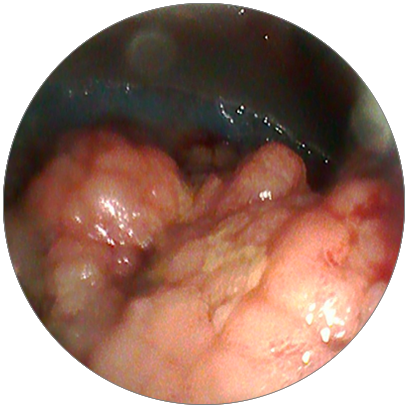

對(duì)以上可疑處取樣

進(jìn)行病理檢查

很快結(jié)果反饋回來

管狀腺瘤伴中度異型增生

由于該腫物范圍較大

且存在惡變的風(fēng)險(xiǎn)